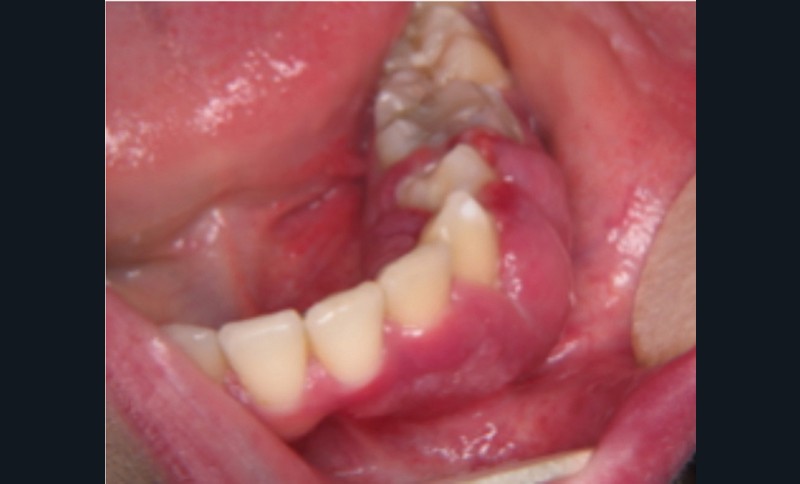

Examen clinique. Sous le maquillage, l’inspection exo-buccale révélait sur la joue gauche une lésion angiomateuse de couleur rouge. L’examen endo-buccal montrait un accroissement gingival violine qui s’étendait de 31 à 36. La palpation mettait en évidence une lésion légèrement molle, non pulsatile, saignant facilement.

Examen paraclinique. Une biopsie a été réalisée et l’examen anatomopathologique a révélé de nombreuses cavités vasculaires de taille variable dont la paroi mince était constituée d’un simple endothélium ; cet aspect est compatible avec celui d’une malformation veineuse.